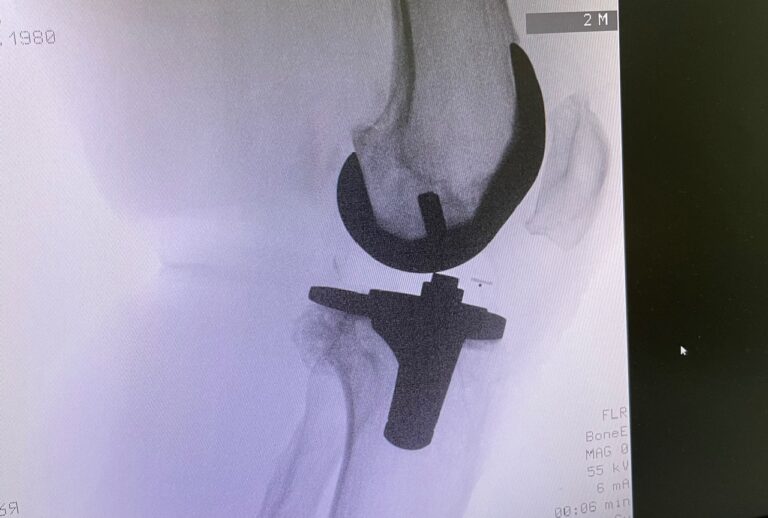

Η ολική αρθροπλαστική γόνατος είναι χειρουργική επέμβαση κατά την οποία αντικαθίσταται η φθαρμένη άρθρωση του γόνατος με τεχνητά εμφυτεύματα.

Στόχος είναι η ανακούφιση από τον πόνο, η βελτίωση της κίνησης και η αποκατάσταση της λειτουργικότητας του γόνατος.

Κατά την ολική αρθροπλαστική:

• αφαιρούνται οι φθαρμένες αρθρικές επιφάνειες

• τοποθετούνται μεταλλικά εμφυτεύματα στο μηριαίο οστό και την κνήμη

• παρεμβάλλεται ειδικό ένθετο πολυαιθυλενίου

• σε επιλεγμένες περιπτώσεις αντικαθίσταται και η επιγονατίδα